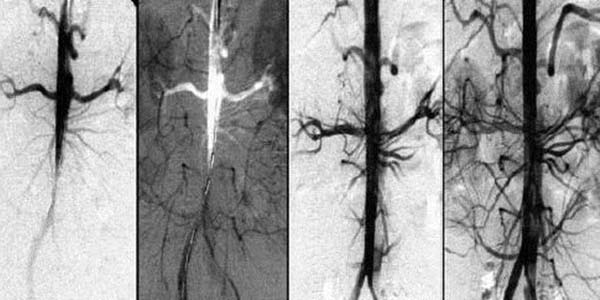

Segít feloldani az ateroszklerotikus plakkokat, a vérrögöket és a kalciumot. Segít az érlumen 99,71%-ra történő növelésében és a véráramlás helyreállításában.